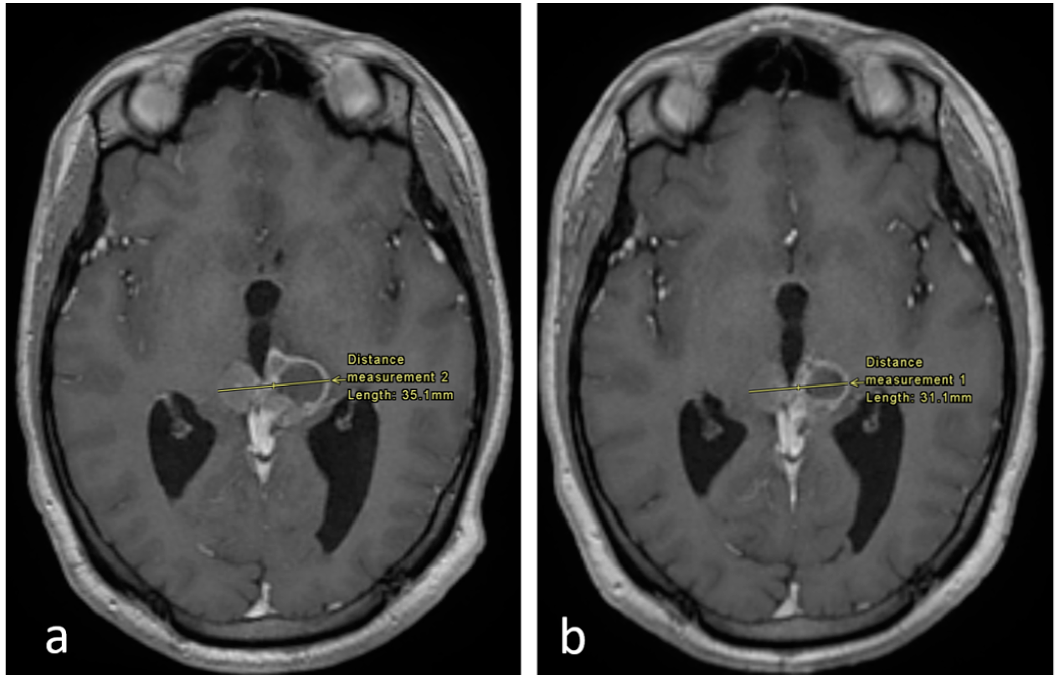

Follow-up MRIs after 6 and 9 months of treatment in December 2017 and March 2018 revealed reductions in the solid components of both the cerebellar and pineal masses, despite an increase in the cystic component and persistent hydrocephalus (Figure 1 and Figure 2). Since the patient was asymptomatic, dexamethasone was discontinued at that point.

Figure 2. Axial enhanced T1 weighted images of the brain at the level of the pineal region. (a) Imaging performed in September 2017 and (b) in December 2017. There is an interval decrease in the size of the tumor, as shown.